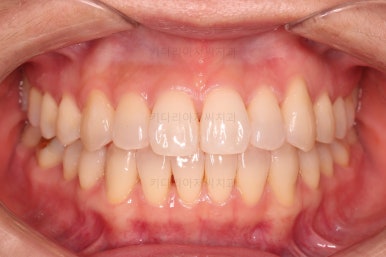

4. 마무리

철사교정과 마찬가지로 앞니쪽에 유지장치를 구성하고 치료를 종료합니다.

매우 가지런해졌고요.

맞물림도 좋아졌고, 중앙선도 잘 맞춰졌습니다.

부산인비절라인 전후 비교해 보겠습니다.

입매를 유지하면서 비발치이더라도 입이 더 나오지 않게 마무리 했고요.

가지런한 느낌 좋고, 중앙선이라던지 교합도 좋아졌습니다.

장치 제작기간 제외하면 약 19개월 정도 소요된 부산인비절라인 치료였습니다.